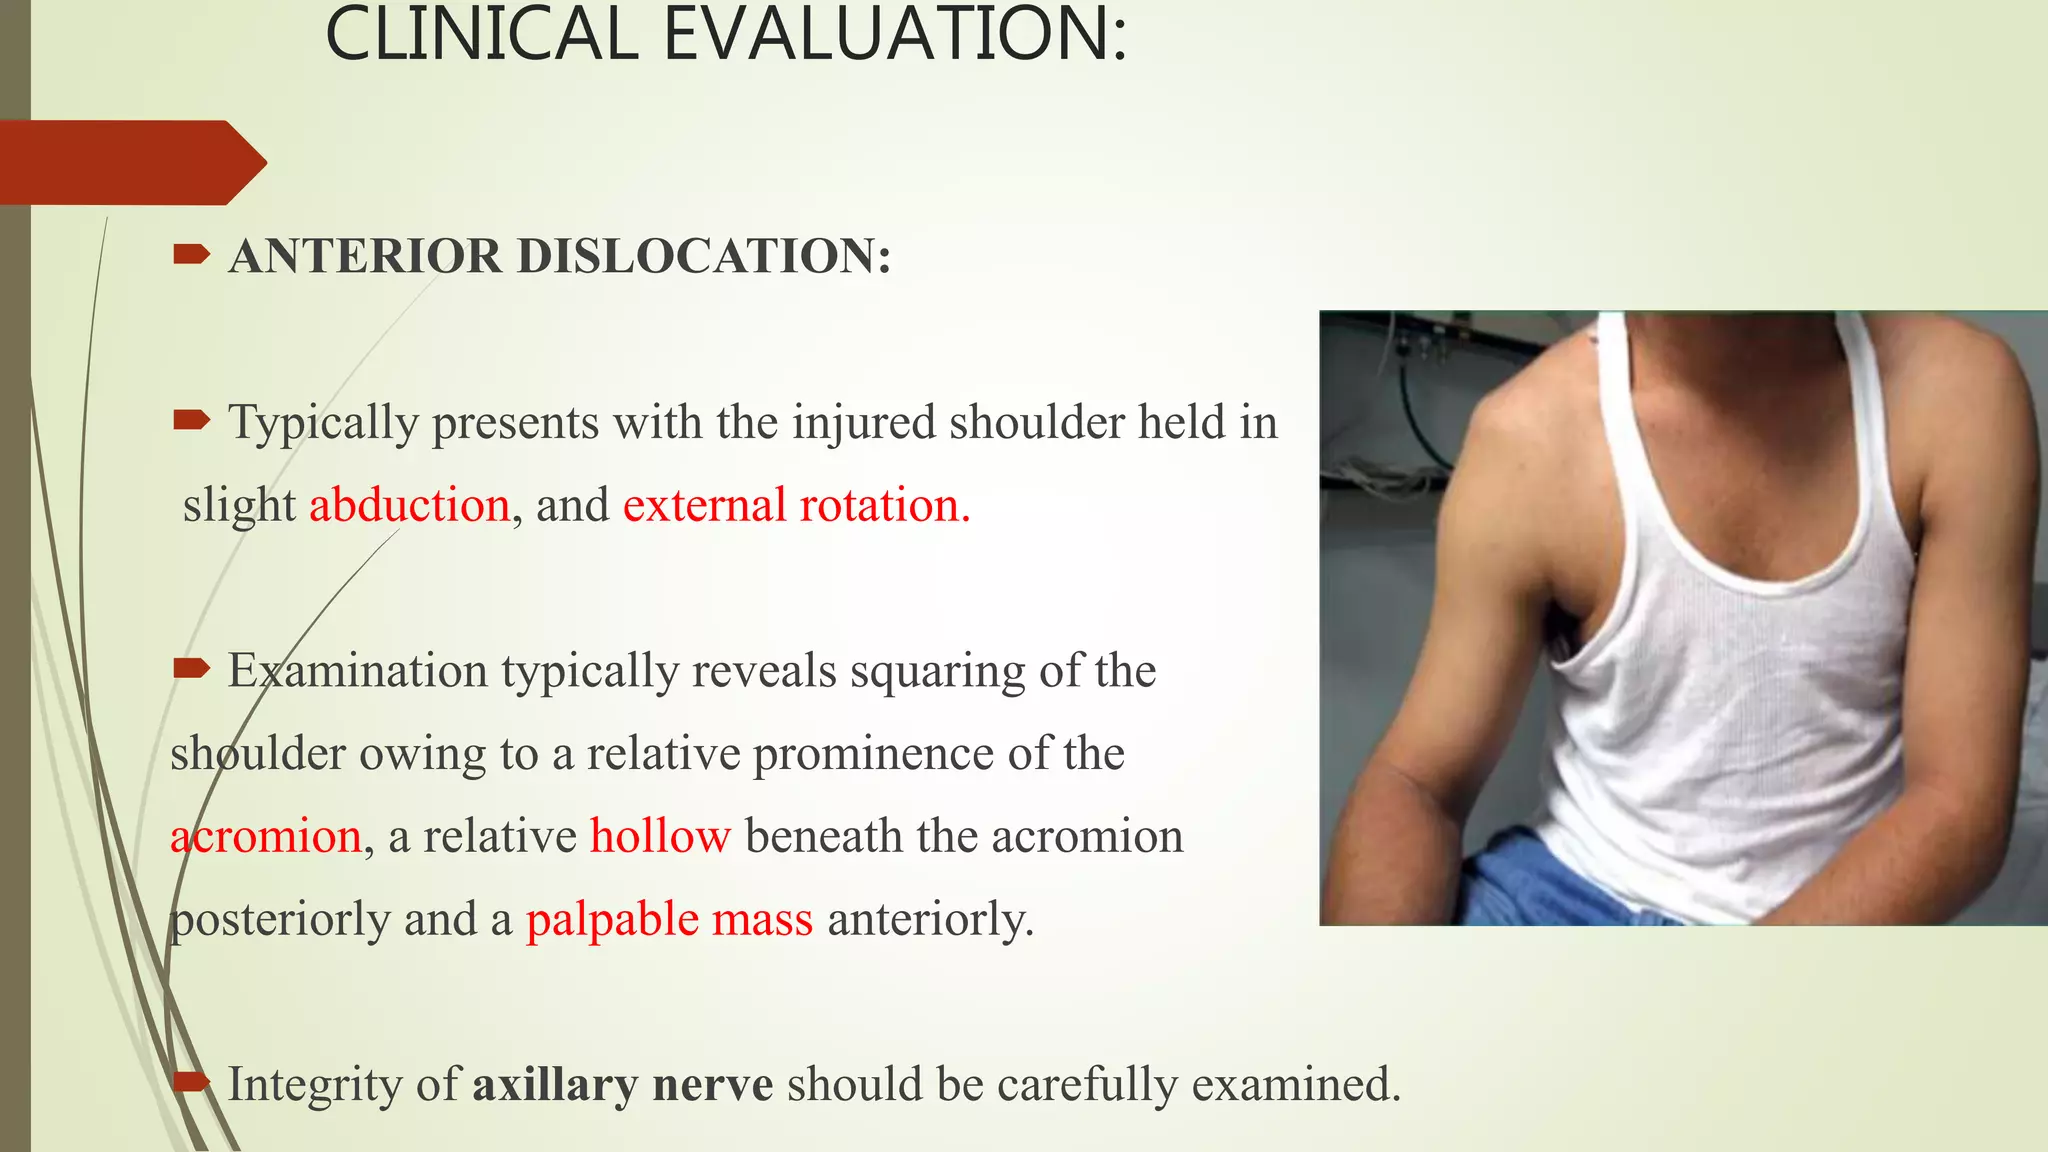

- Clinical evaluation and radiographs are used to diagnose the type of dislocation and assess for complications like fractures.